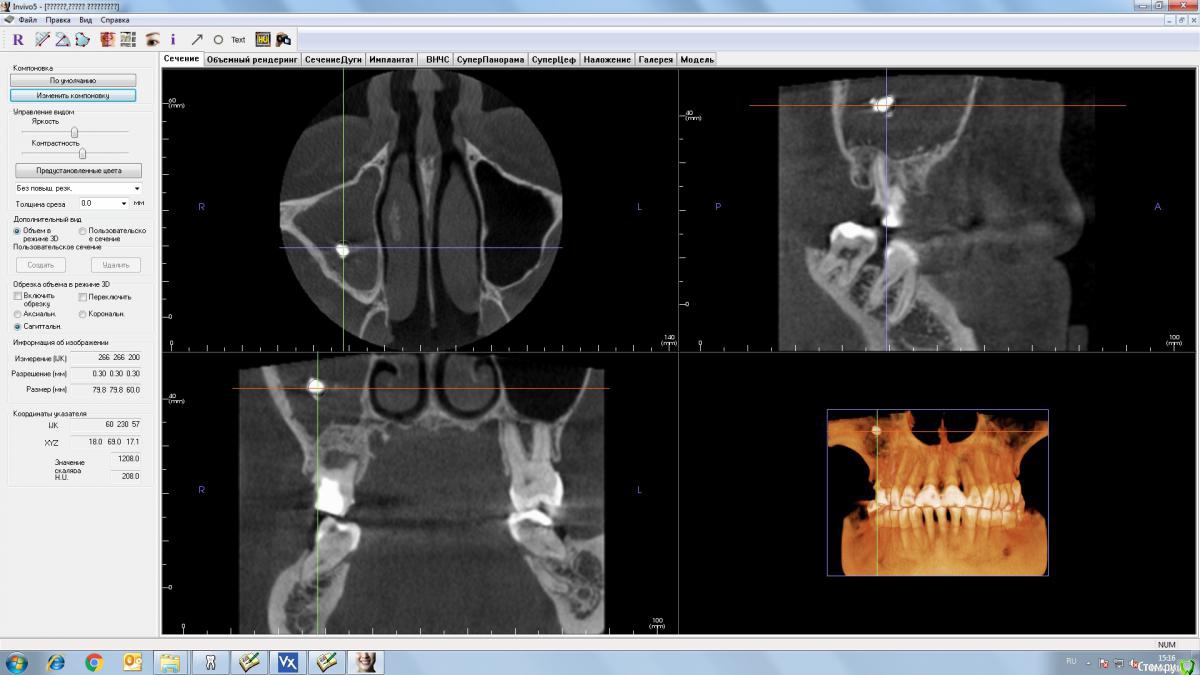

TIGER Опубликовано 19 июля, 2016 Поделиться Опубликовано 19 июля, 2016 1 вариант...там грибы в пазухе Ссылка на комментарий

AlexanderGudkov Опубликовано 19 июля, 2016 Поделиться Опубликовано 19 июля, 2016 Я бы сделал так:Эндоскопическая эндоназальная гайморотомияУдаление зубов, винты на уровнях 14,16 с закрытым синусомПотом можно и 17 доставить Немножко без зубов потдется побыть.. Ссылка на комментарий

Slaggy Опубликовано 19 июля, 2016 Поделиться Опубликовано 19 июля, 2016 Уважаемые коллеги, хотел бы получить совет и ваше мнение, как на данную ситуацию. Пациент изначально отказался от ортодонтического лечения. По плану:1. вариантвизит ЛОР, ( какие ждут пациента манипуляции???)после чего удаление 15, 17 зубов, возможно закрытие ороантрального соустья.Через 6 месяцев имплантация и далее все по плану. 2 вариант.Была мысль поставить 14, 16 (с закрытым синусом) импланты, провизорную конструкцию, через 3 недели удаление 15, 17.Через 6 месяцев установка 15,17 импланты. Смущает только возможность обострения 15 и 17 зубов после имплантации 14,16.Так как я относительно молодой хирург-имплантолог, прошу совета, может есть какие-то другие варианты.И хотелось бы узнать, если мы будем двигаться по первому плану, то какую конструкцию в качестве временной можно использовать? Точнее лучше использовать.А на какие риски готовы пойти? Если грибы - может получиться epic failИМХО - Вероятно грибы. Лор с эндоскопом - обязательно. Лечение пазухи санация зубов, 2-3 месяца пауза. Контрольное КТ, принятие решения о лифтинге и имплантации. Ссылка на комментарий

stommm Опубликовано 19 июля, 2016 Поделиться Опубликовано 19 июля, 2016 1)Если 15 и 17 восстановлению не подлежат, то удаление и к ЛОРУ. 2) если в области 14 и 16 можно обойтись короткими имплантами без синуса, то сразу после Лора можно или даже сразу с удалениями. Если синус необходим, то как Лор разрешит3) доставить 17 При наличии имплантов 14,16 и 17, имплант 15 будет очень похож на ипотечный, да и проблем с ним скорее всего будет больше чем пользы Ссылка на комментарий